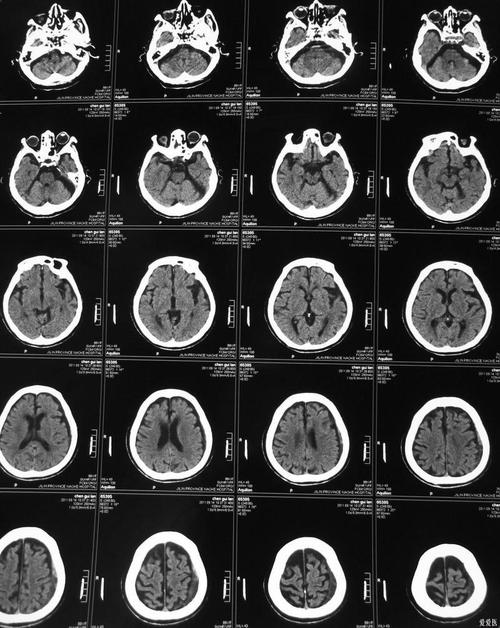

脑CT上显示的“脑梗症状边缘模糊”是急性期脑梗死的典型影像学特征之一,但它并不能作为确诊脑梗死的唯一依据。

在正常的脑CT影像上,大脑的灰质(细胞体聚集的地方)和白质(神经纤维束)之间有比较清晰的分界,当发生脑梗死后,这个分界会变得模糊不清,主要原因是:

- 细胞水肿(细胞毒性水肿):这是最核心的原因,脑组织缺血缺氧后,脑细胞无法维持正常的离子平衡,导致大量水分涌入细胞内,细胞像气球一样“肿胀”起来,这种肿胀的细胞会压迫周围的正常组织,使得原本清晰的解剖边界变得模糊。

- 血管源性水肿:随着缺血时间延长,血脑屏障(保护大脑的一道“墙”)被破坏,血管里的液体会漏到细胞间隙中,进一步加重水肿和边界模糊。

“边缘模糊”是脑组织正在发生缺血性损伤的早期信号,表明梗死的范围可能还在扩大,或者处于非常活跃的病理变化阶段。

- 发现早期大梗死灶:对于大脑中动脉等大血管堵塞引起的大面积脑梗死,CT在发病后数小时内就可能显示出一些间接征象,比如脑沟变浅、脑回模糊、密度稍低等,这些都是“边缘模糊”的宏观表现。